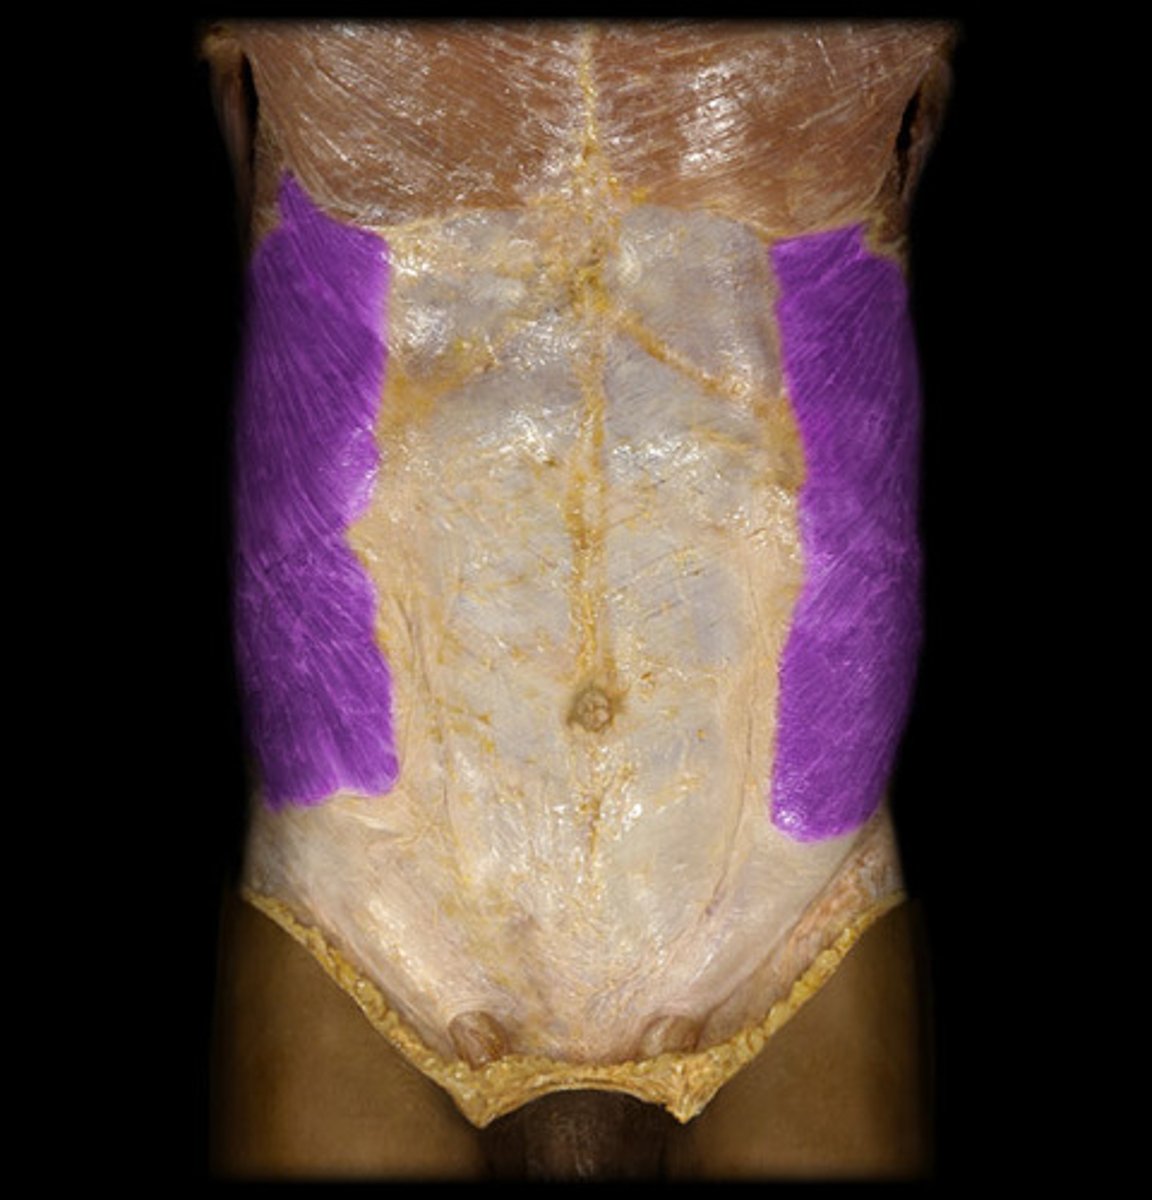

What is this?

Rectus abdominis

Linea alba

Rectus sheath

Lineae semilunares

External oblique

Internal oblique

Transversus abdominis